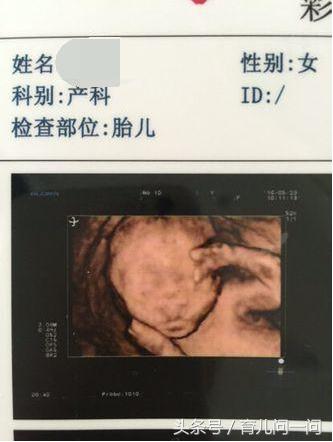

女儿九岁了,经过长时间的思想斗争终于决定要二胎,今年二月,大年初二取了环,为了要男宝开始吃素,一天三顿的冒菜(自己在家冒的),一点主食和荤腥都不见,本想四月再开始怀,这样孩子能生到明年上半年,另外我本身在五年前宫外孕手术过,还担心怀不上,没想到去环一个月就意外怀孕了。反正是吃了一个月的素,最后尿的尿不用测酸碱度肉眼看都是绿的。怀孕后四个月、五个月、7个月分别找熟人在不同医院看过男女,都确定是男孩